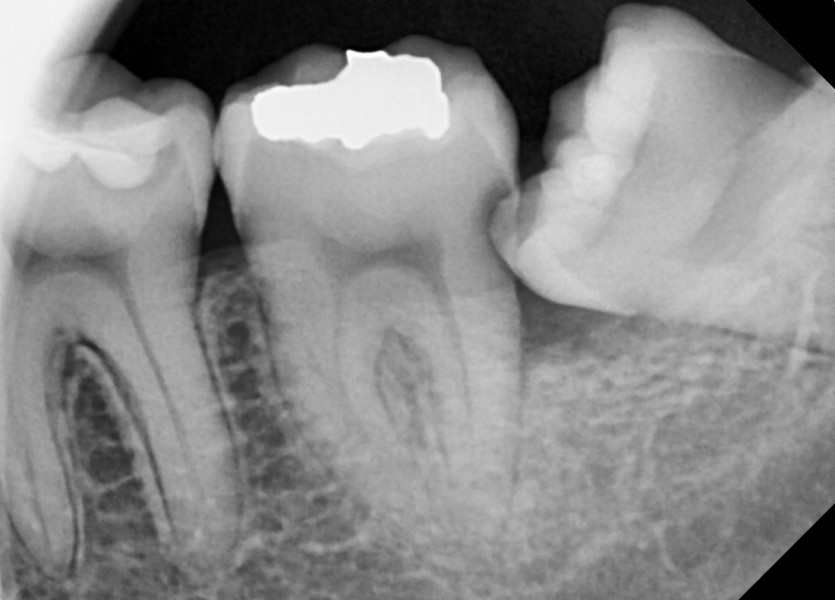

#38 사랑니 발치

구강 외과 전문의가 당일 발치했습니다.